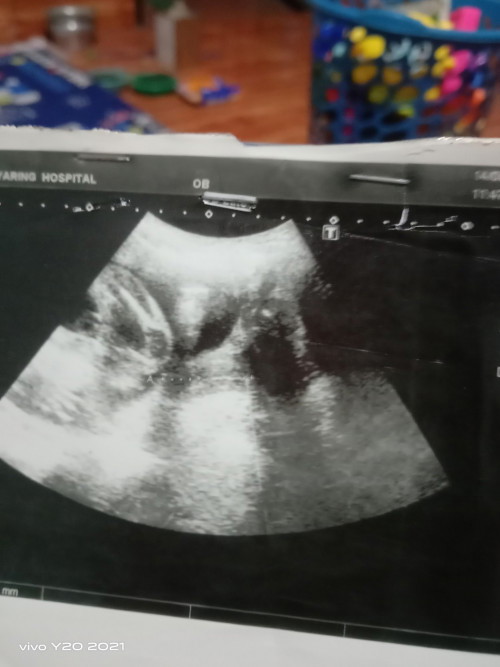

ไปซาวมาแล้วคุณหมอบอกน้องเป็นผู้หญิง แต่ทำไมเราเห็นตุ่มๆเหมือนไข่เลยคะ มีแม่ๆคนไหนได้รูปผลซาวประมานนี้แล้วเป็นผู้หญิงบ้างคะ แล้วผลซาวผู้ชายประมานไหนคะ 🤣